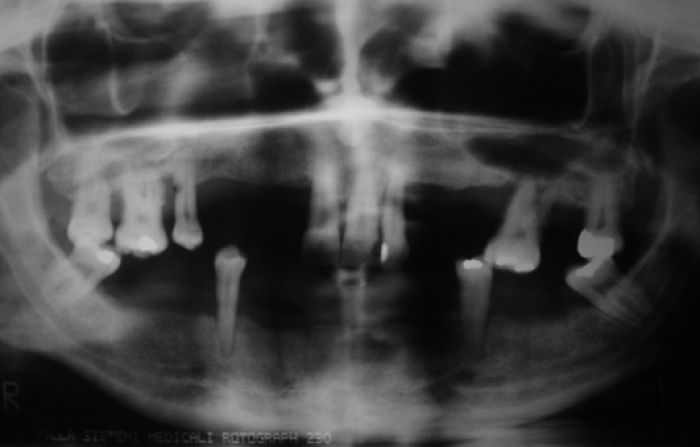

Raio X inicial